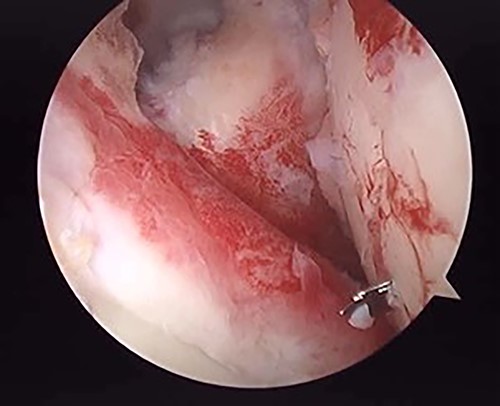

The operation was performed under general anesthesia with an ultrasound-guided brachial plexus block in the beach chair position. First, we performed intra-articular observation by arthroscopy with a 30° scope. Through a posterior portal, we confirmed incongruence of the articular surface of the humeral head, similar to the preoperative findings in 3D-CT (Fig. 4). On the other hand, the posterior joint labrum and glenoid rim were intact. After evaluating the intra-articular lesion, we performed arthroscopic reduction for the impression fracture at the humeral head via the arthroscopic method [5,6]. We split the deltoid muscle and exposed the lateral surface of the humerus. We inserted a Kirschner wire as a reduction guide 2 cm distal from the upper border of the greater tuberosity and 2 cm behind the bicipital groove (Fig. 5). Kirschner wire was inserted to exit the impression lesion while checking the articular surface with an arthroscope (Fig. 6). We created a cortical window (approximately 10 × 10 mm) using a cannulated drill with the Kirschner wire as a guide. To reduce the impression, we pushed the back of the impression using the flat side of the canulated cancellous screw (CCS) drill. After the reduction, artificial bone was inserted from the cortical window to the subchondral bone region to provide support for the depressed area. We then performed a procedure to insert a support screw into the articular surface. The deltopectoral approach was used. First, we dissected the subacromial bursa entirely while visualizing the conjoint tendon. Next, we detached the long head of the biceps at the bicipital groove and sutured it to the pectoralis major muscle. Two CCSs were inserted from the bicipital groove to under the repaired humeral head as support for the reduction site. Finally, after arthroscopic reduction, we performed ORIF for surgical neck fracture using a PHILOS Plate™ (DePuy Synthes).

Posterior arthroscopy of the right shoulder joint. The right is the humeral head side, and the left is the glenoid side. Impression of the humeral head was noted, but the posterior labrum was not damaged.